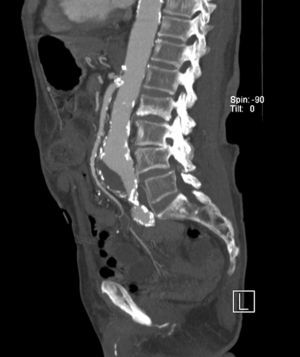

Fig. 7. Imagen de reconstrucción de máxima intensidad de proyección (MIP) sagital (A) y volume rending de aneurismas de aorta abdominal infrarrenal (B) de dos pacientes diferentes.

La mejora sustancial de la tecnología multidetector ha permitido el desarrollo de una generación de escáneres con resolución espacial y temporal suficiente como para establecer la angio-TC aorto-iliaca como la prueba diagnóstica de elección en el estudio de la patología aneurismática aórtica abdominal1-4. La reducción progresiva de la duración de los estudios ha obligado a replantearse los esquemas clásicos de administración de contraste11. Con adquisiciones tan rápidas como las obtenidas con el TMC de 16 coronas, aproximadamente 7-8 segundos en una angio-TC aorto-iliaca, la hipótesis es que con volúmenes menores de contraste es posible conseguir niveles de atenuación suficientes para obtener estudios diagnósticos de calidad que permitan la correcta visualización de las arterias (figs. 7A y 7B).